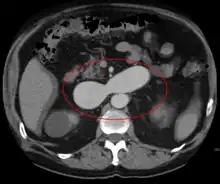

AVMs are diagnosed primarily by the following imaging methods:[12]

- Computerized tomography (CT) scan is a noninvasive X-ray to view the anatomical structures within the brain to detect blood in or around the brain. A newer technology called CT angiography involves the injection of contrast into the blood stream to view the arteries of the brain. This type of test provides the best pictures of blood vessels through angiography and soft tissues through CT.